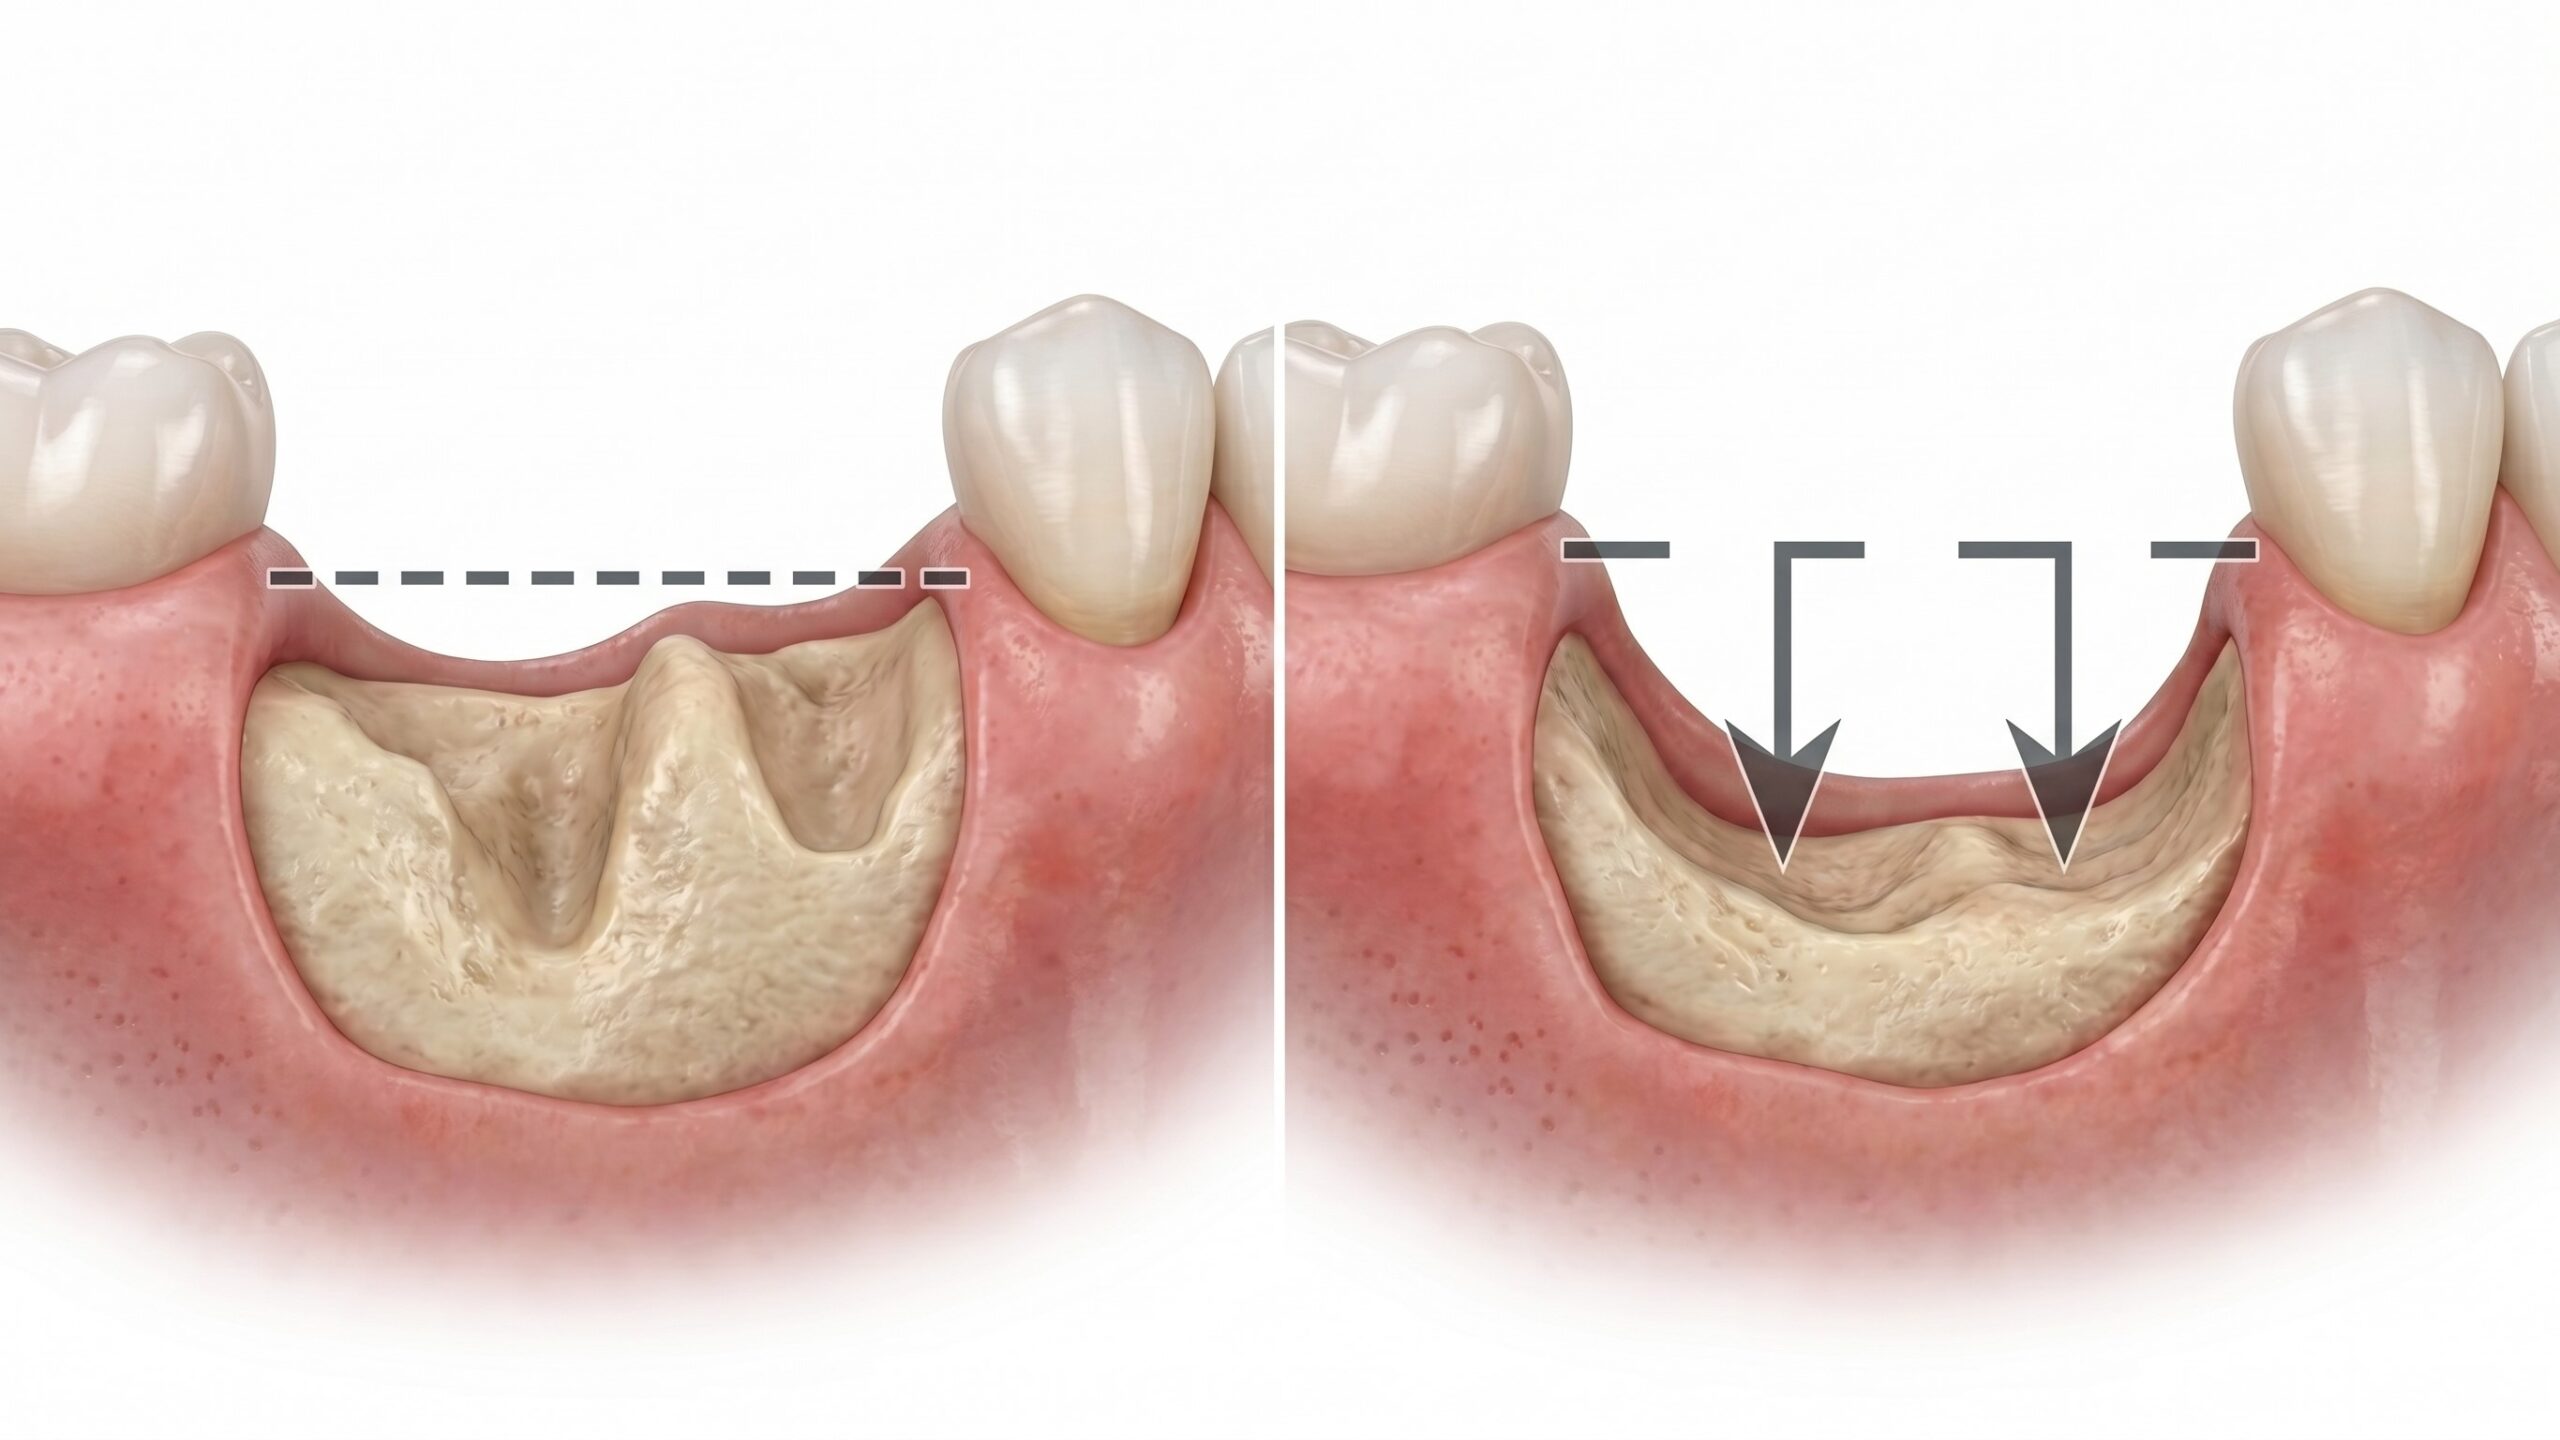

치아를 잃고 나면 그 자리의 뼈, 즉 치조골은 서서히 흡수되기 시작합니다. 자연치아의 씹는 자극이 사라지면서 뼈가 더 이상 유지될 이유를 잃기 때문입니다. 발치 후 6개월이면 수평적으로 25% 이상, 1년이면 최대 40%까지 골량이 줄어들 수 있다는 임상 데이터가 있습니다. 임플란트는 이 치조골에 고정되어야 하기 때문에, 뼈의 양과 밀도가 충분하지 않으면 식립 자체가 불가능하거나 장기적인 성공률이 현저히 낮아집니다.